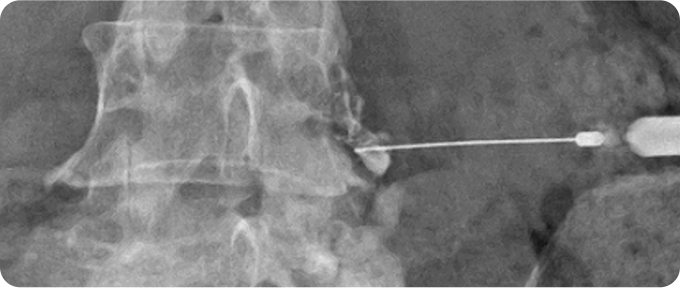

신경성형술 사진

2

신경성형술

특수한 카테터를 사용하여 신경 주위의 유착을 풀고 염증을 완화하는 비수술적 치료법입니다. 이 방법은 신경 압박을 해소하여 통증을 줄이고, 허리디스크와 척추관 협착증 등 다양한 신경통 치료에 효과적입니다. 절개가 필요 없으며 회복 기간이 짧아 부담이 적습니다. 다만, 환자 상태에 따라 적합 여부를 전문의와 상담하는 것이 중요합니다.